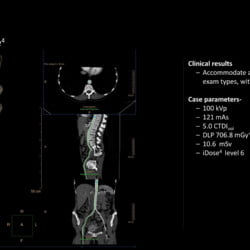

Incisive CT de 64 canais e 128 cortes

Especificações Técnicas do Tomógrafo Philips Incisive CT

| Tipo de tubo | Tubo vMRC Cerâmico |

| Capacidade do tubo | 8 MHU |

| Configuração de kVp | 70, 80, 100, 120, 140 kV |

| Tamanho do bore | 72 cm |

| Cortes | até 128 cortes |

| Cobertura | 40 mm |

| Potência do gerador | 80 kW |

| Velocidade de rotação | até 0,35 s |